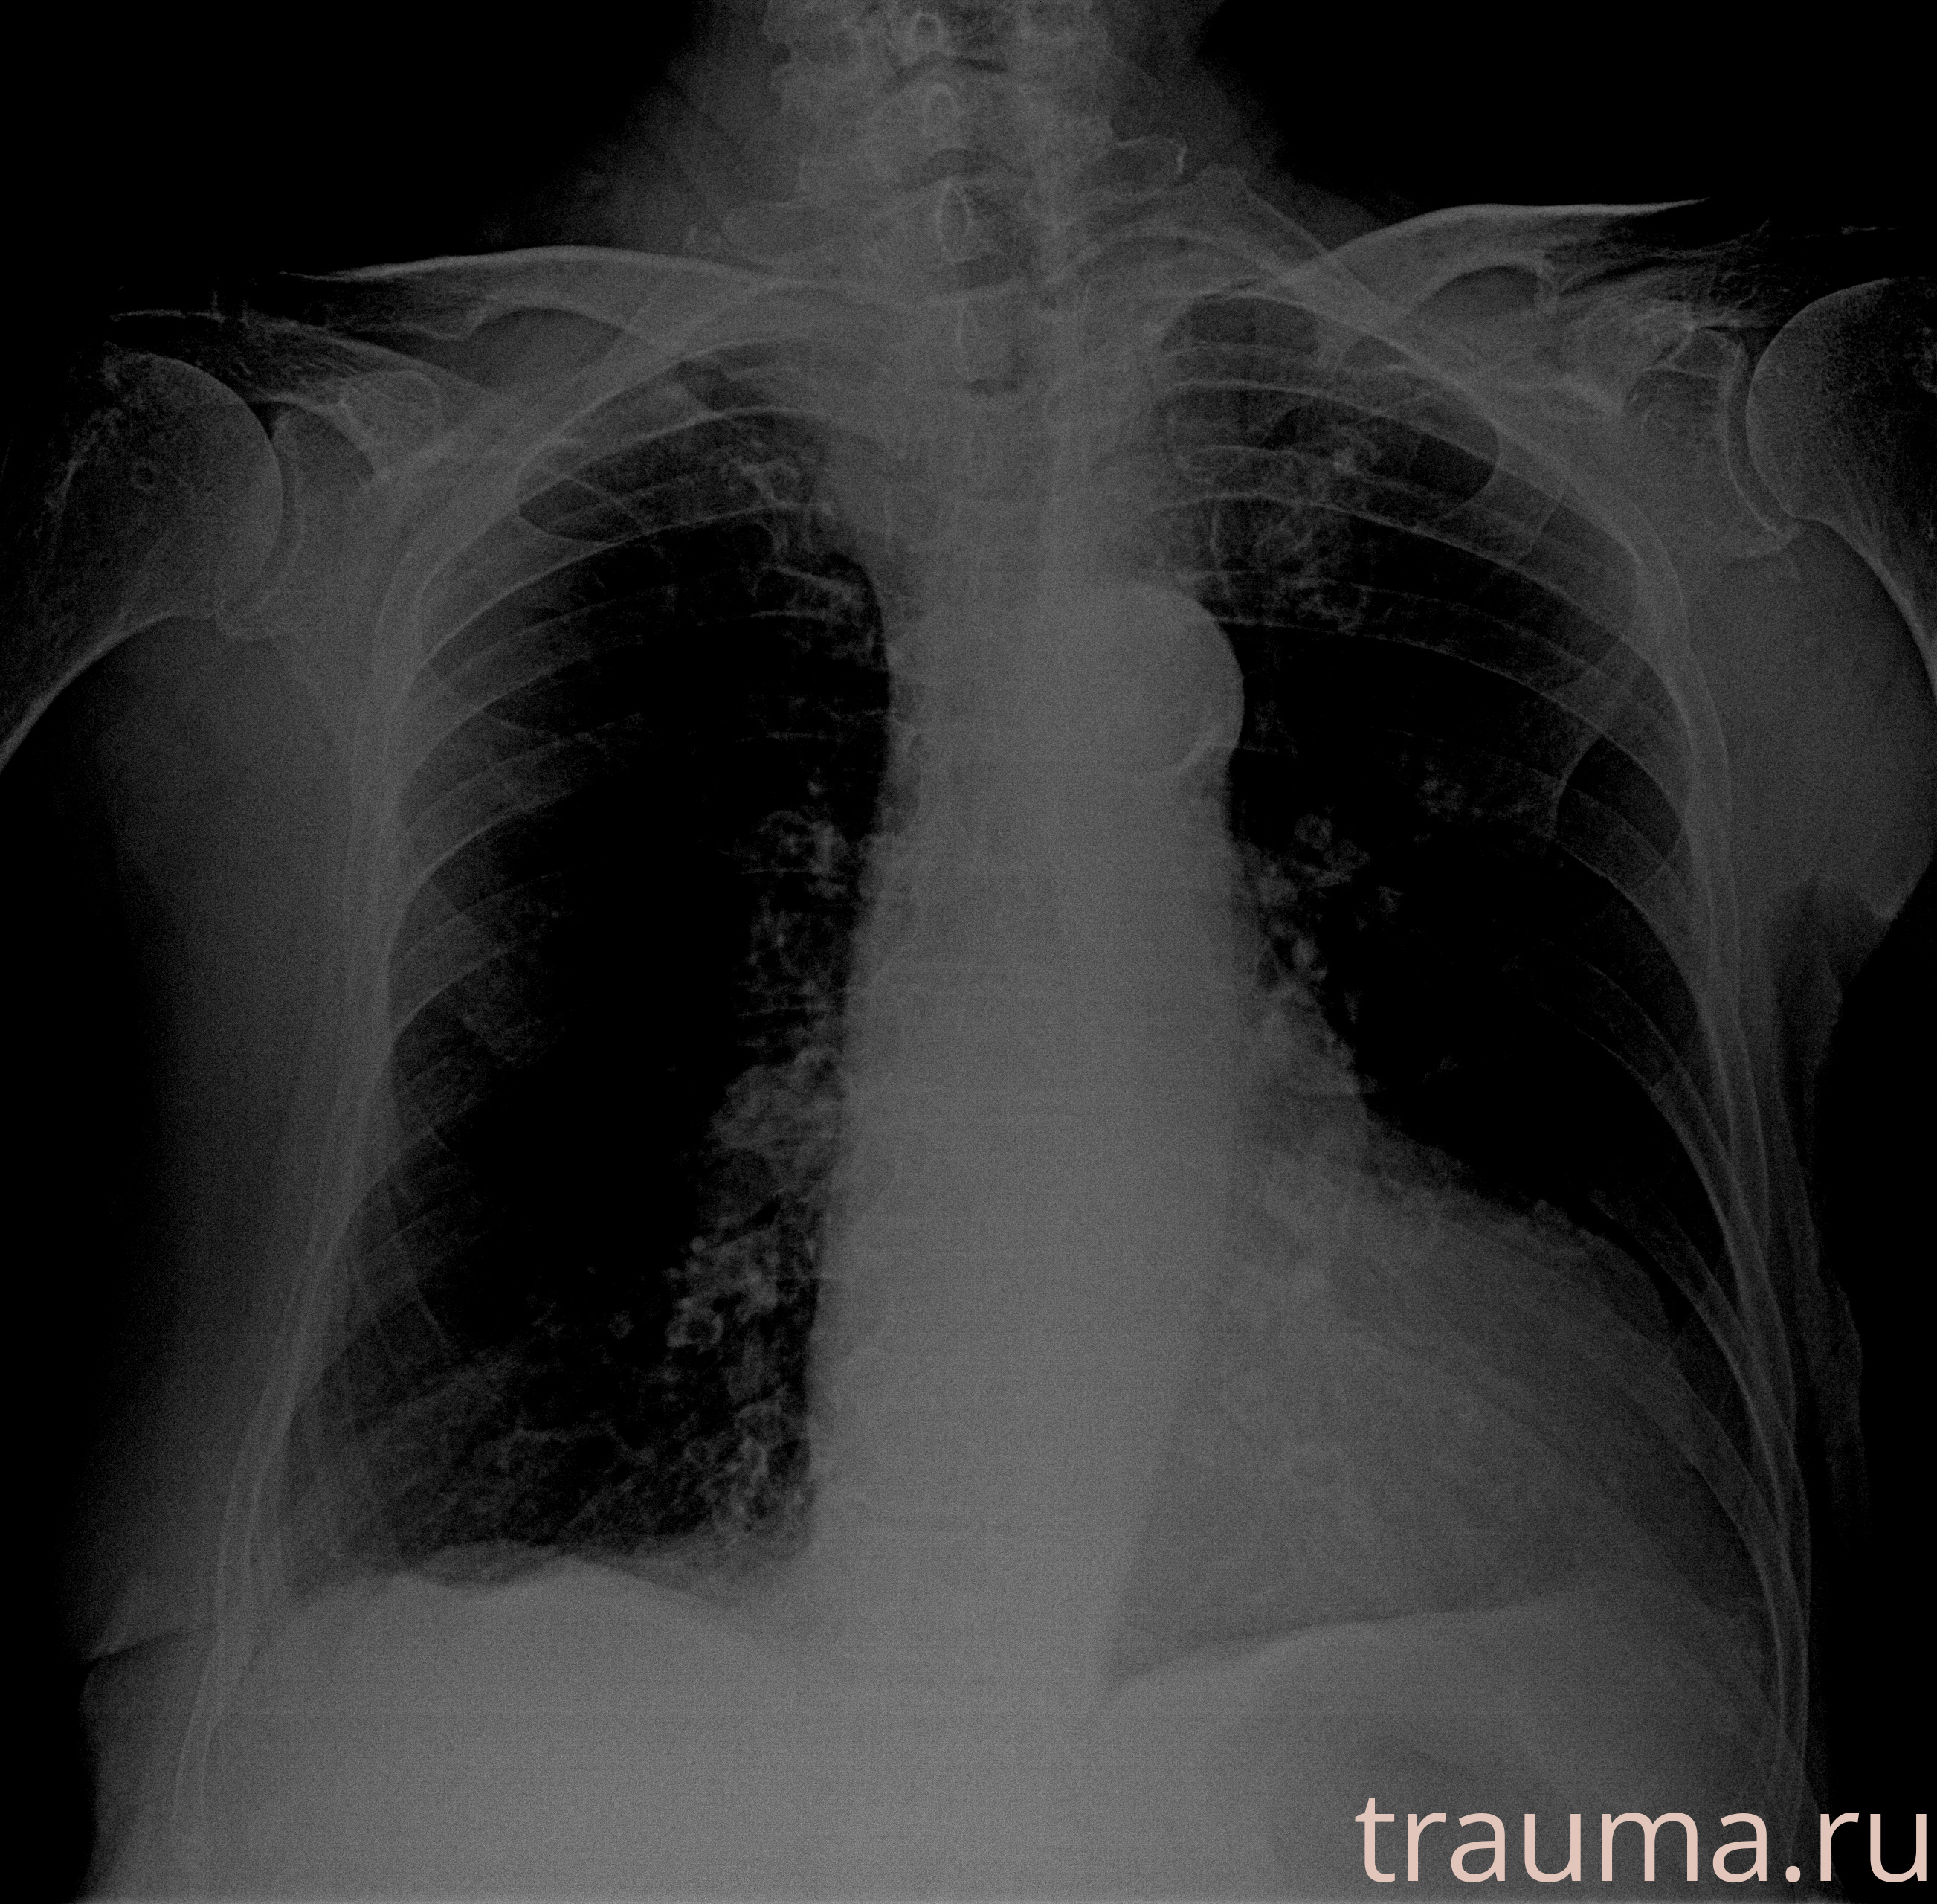

Рентген на дому: по вашему адресу приезжает врач-рентгенолог, травматолог-ортопед с мобильным рентгеновским аппаратом, проводит диагностику травмы или заболевания, делает необходимые рентгенограммы, дает рекомендации по дальнейшему лечению. Получить качественные снимки в домашних условиях возможно благодаря уникальной методике, разработанной МосРентген Центром для института  Склифосовского